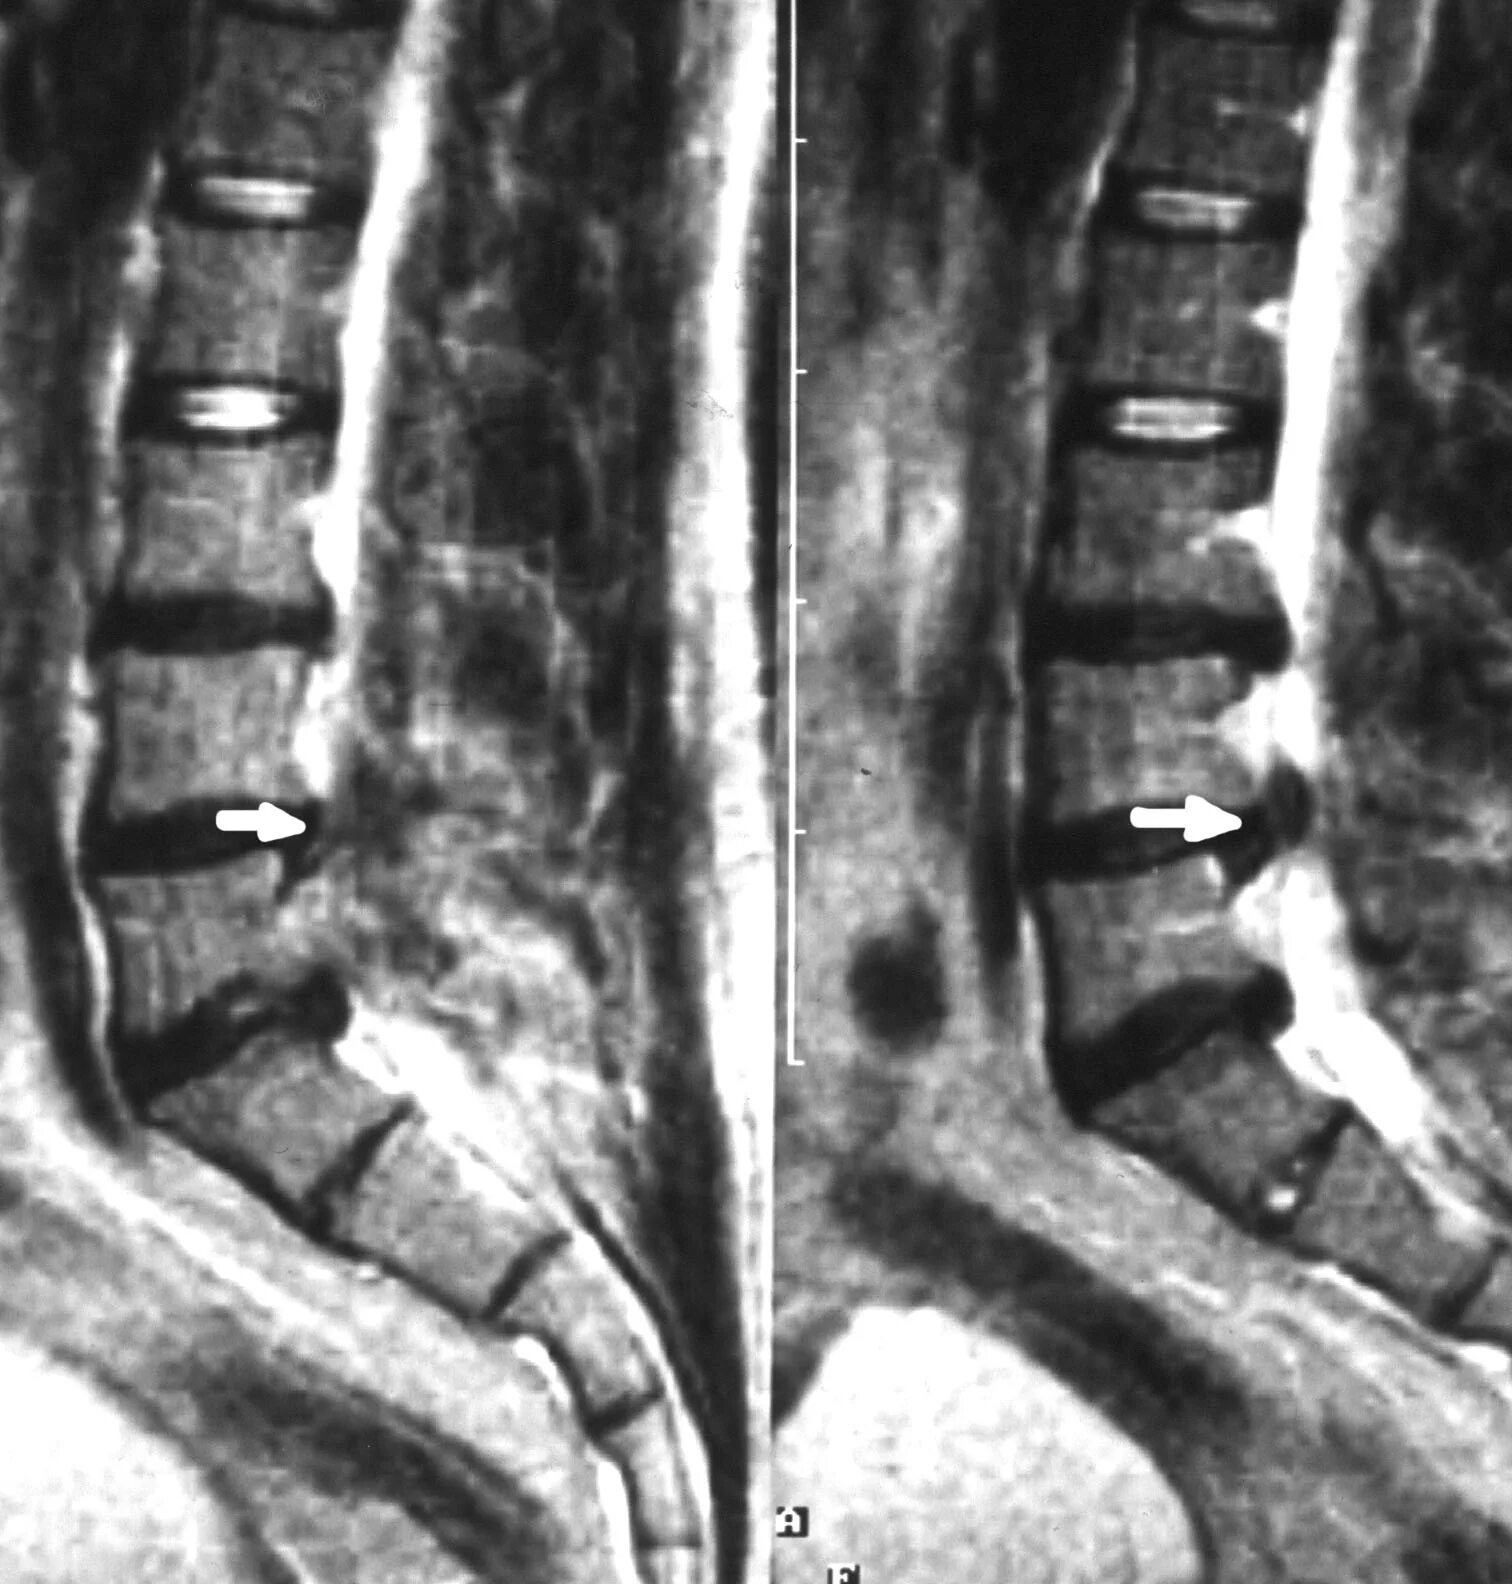

Протрузии l3 4 l4 5